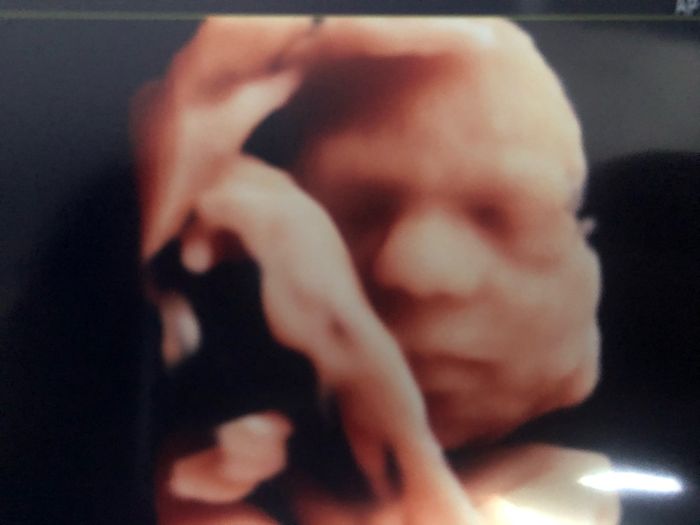

Future mamme novembre 2020 ๐๐๐ทโพ

Da Lalla , Il 3 Settembre 2020 alle 14:12

ECCO CHI SIAMO E CHI SONO I NOSTRI AMORI ETERNI...